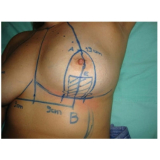

Mamoplastia de Elevação

Se você não sabe onde encontrar bons profissionais, equipe médica compromissada e sempre pronta a atender bem o seu cliente? Pois não se preocupe mais pois a FF Cirurgia Plástica coloca à disposição do cliente a possibilidade de contratar assistência médica pertinente que o possibilite submeter-se à mamoplastia de elevação.

Não pense duas vezes: conheça o consultório médico que realiza mamoplastia de elevação!

Praticidade pensada no que é mais adequado às necessidades do cliente, com profissionais de saúde por perto, levando maior segurança e eficiência até você. Busque com essa equipe todas as informações que precisa e saia satisfeito e tranquilo! Qualidade e bom atendimento você encontra de excelência na FF Cirurgia Plástica.